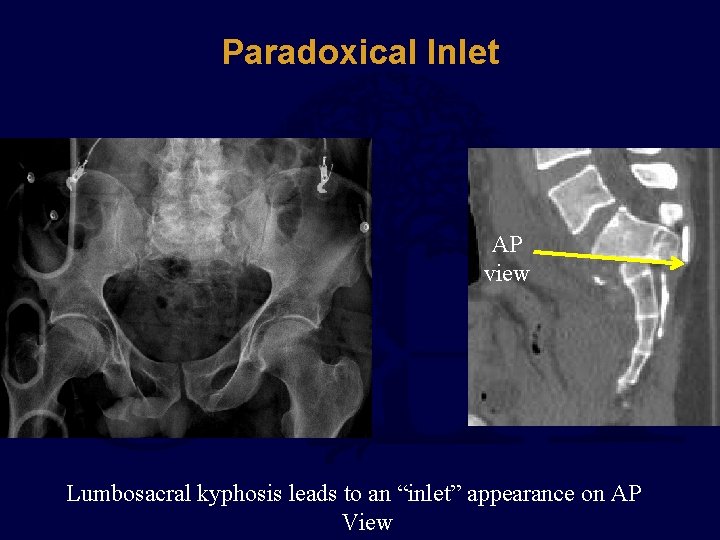

Paradoxical Inlet AP view Lumbosacral kyphosis leads to an “inlet” appearance on AP View